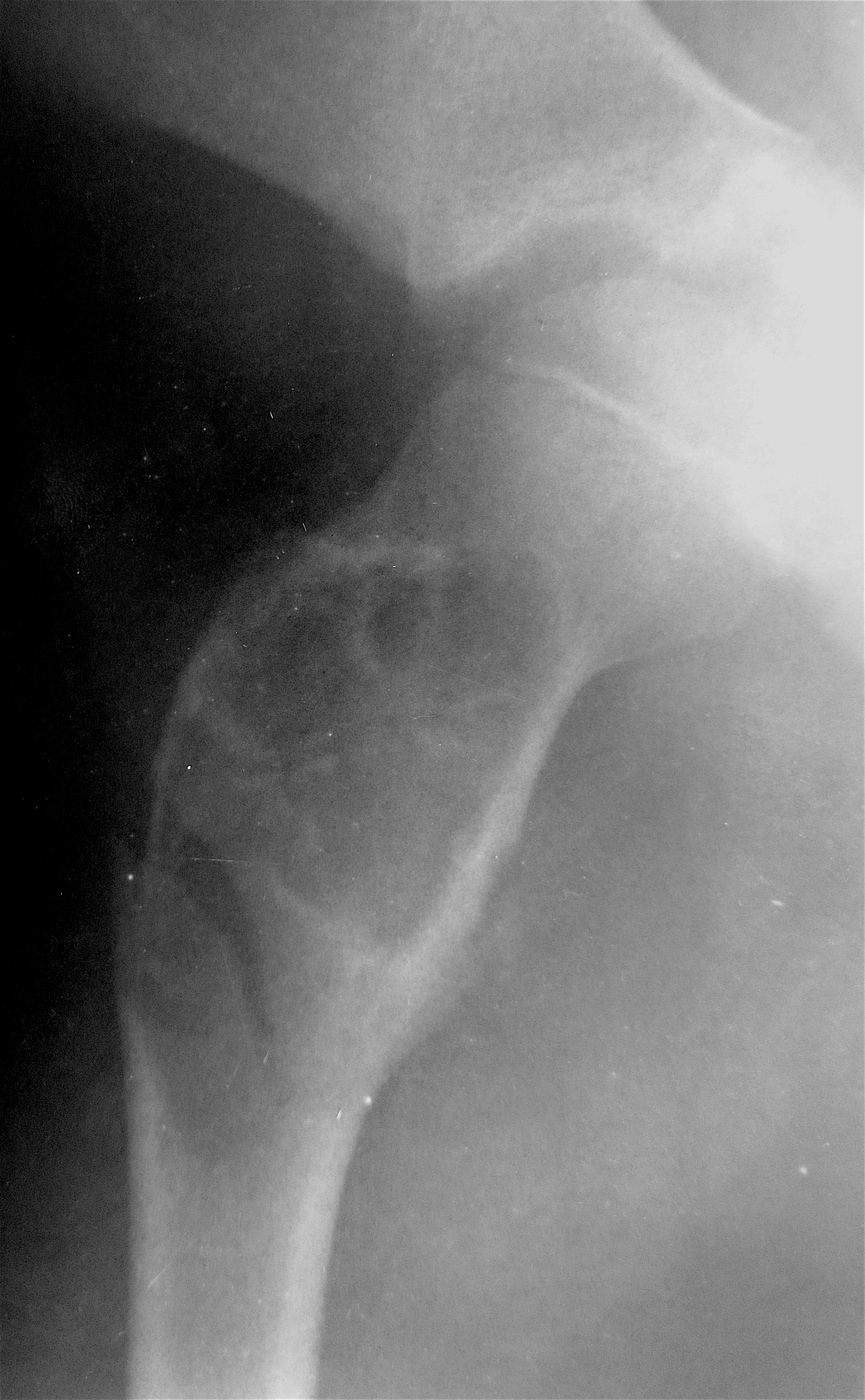

Закрытый, паталогический перелом в подвертельной области правой бедренной кости со смещением, на фоне аневризмальной костной кисты.

Выполнена резекция с аллопластикой губчатыми и кортикальными биоимплантатами "Лиопласт".